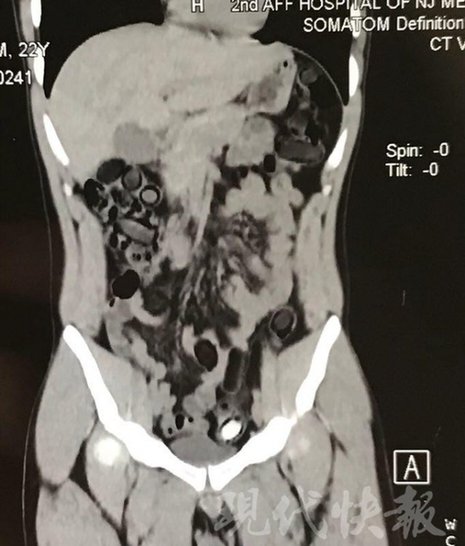

运毒小伙:希望被判处死刑

由于毒品在体内一旦泄露有可能致命,警方第一时间将阿永带到医院进行检查。CT 扫描的结果显示,阿永体内布满了密密麻麻的白色圆柱状固体,就像一粒粒的蚕蛹。在南京市公安局鼓楼分局二板桥派出所,阿永分四次排出了毒品,毛重369.99 克。经讯问,阿永交代了自己全部的犯罪事实。目前,阿永已被刑事拘留。